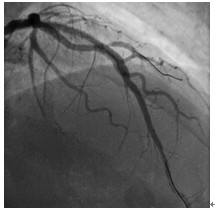

图4 前降支中段原支架内狭窄消失,远端未见夹层。